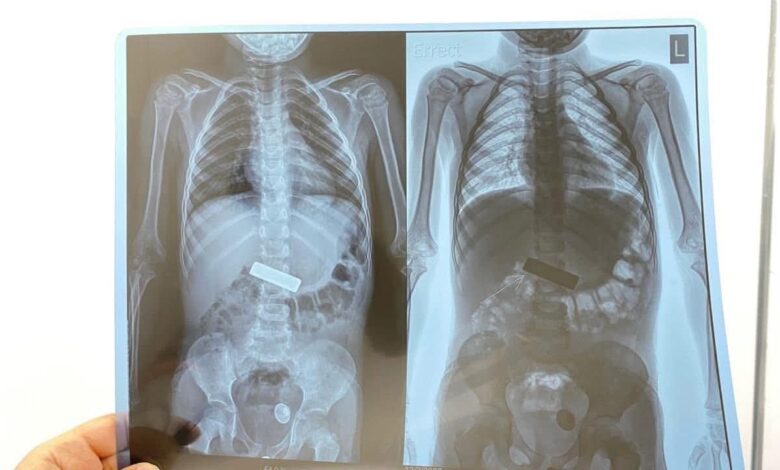

وبعد إجراء الفحوصات العاجلة تبيّن وجود جسم معدني حاد عالق في المريء تسبب بتهيّج شديد ونزف داخلي.

وعلى الفور تم استدعاء الفريق الطبي وإدخال الطفلة إلى صالة العمليات الناظورية حيث أُجري لها ناظور تحت التخدير العام

وتمكّن الدكتور أحمد جاسم الكوفي—الاستشاري في أمراض وجراحة الجهاز الهضمي

من استخراج القطعة المعدنية وإنقاذ حياة الطفلة قبل حدوث مضاعفات خطرة.